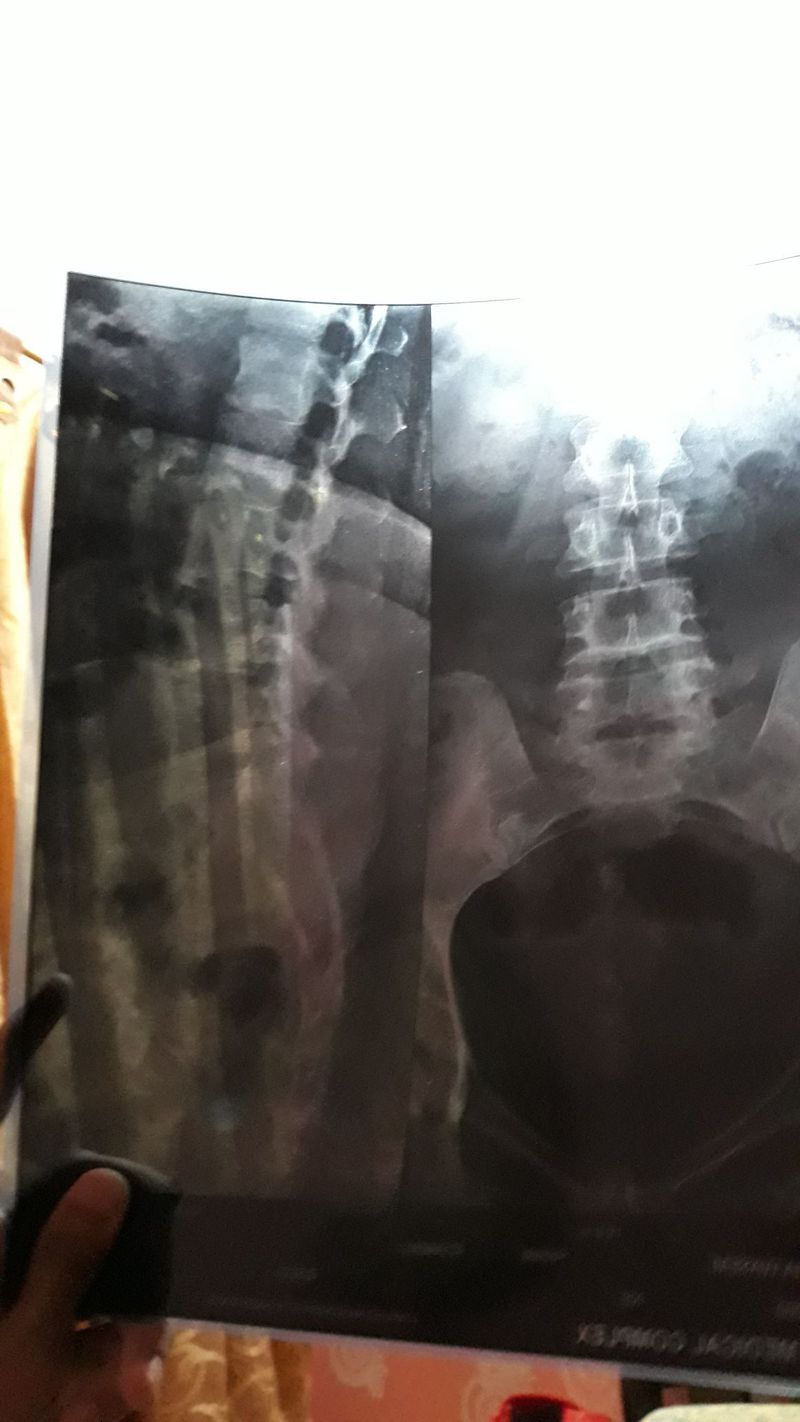

Is there any disc slip?

Xray of 44 years old female

A/P is not bad, post lat. Xray again

And u know that it’s hard to be sure about disc problems with xray. ct is better than this